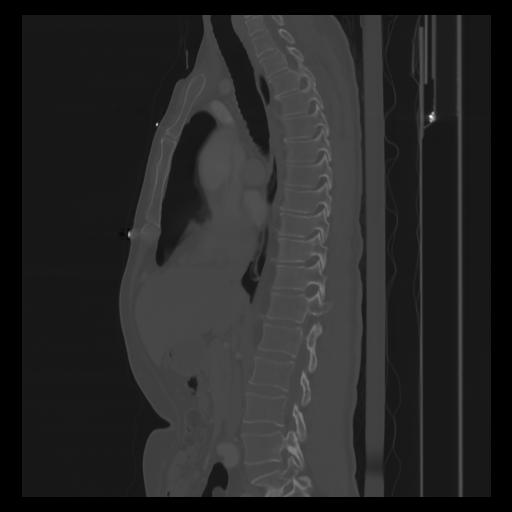

30 CUERPO,CE,Sagittal,3.000,CUERPO,Sagittal,